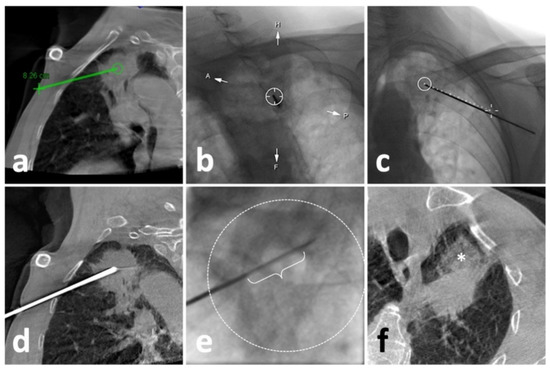

2.4. CBCT Guidance in Lung Biopsy

A rotating angiography system (Artis Zee, Siemens Healthcare, Erlangen, Germany) was used to obtain 3D chest CBCT images during the procedure. Similarly, the patient was asked to hold a breath after a full aspiration during the initial image acquisition. A 6 s rotational scan generated 397 projection images with an angular step of 0.5° and a pulse length of 3.2 ms. A tube voltage of 90 kV with a current of 273.5 mA was set up. Then, the projection images were automatically transmitted to a post-processing workstation (Syngo X Workplace, Siemens Healthcare) for multi-planar reconstruction (MPR) of axial, sagittal, and coronal orientations and 3D volume reconstruction. In the next step, the needle path was set up using a commercial plug-in (Syngo iGuide, Siemens Healthcare) [15,16]. After manually selecting the skin entry point and target lesion position in MPR (Figure 2a), a virtual path with displayed angulation and length was generated and overlayed to real-time fluoroscopy to navigate the puncture process. Then, the operator rotated the C-arm to the Bull’s Eye View and turned on the laser navigation system on the flat panel to locate the skin entry point (Figure 2b). After dermal sterilization, draping, and local anesthesia, the patient was asked to hold a breath again. Then, under real-time fluoroscopy monitoring, a 17 G coaxial needle was advanced along the virtual path until the planned target position was reached (Figure 2c). Afterward, a CBCT scan was re-performed to identify whether the needle repositioning was needed (Figure 2d).

2.5. Lung Biopsy

After achieving an ideal position of the coaxial needle, the stylet was removed. Then, a biopsy instrument (Bard® Max-Core® Disposable Core Biopsy Instrument, 18 G*16 cm, Bard Care, Covington, OH, USA) was advanced to obtain samples (so-called “coaxial cutting needle technique”) (Figure 2e) [10,17,18]. Two to eight samples were obtained based on the pathological and other genetic test demands. Afterward, the needle was removed, and the post-biopsy CT or CBCT was routinely acquired to identify biopsy-related complications (Figure 1c and Figure 2f).

Figure 2. Illustration of C-arm CBCT virtual navigation-guided biopsy. (a), localization of the lesion (solid mass at left upper lobe) and needle route planning (green line); (b), fluoroscopy-guided puncture under virtual navigation at Bull’s Eye View Position; the middle circle indicates the target which was accurately punctured by a 17-G needle; (c), Fluoroscopic check of the needle, which matched perfectly with the virtual path (dash line); (d), a re-examination of CBCT showed eligible needle tip within the solid lesion; (e), the performance of biopsy under real-time fluoroscopy, in which the sampling part of the biopsy instrument (curly bracket) showed appropriate location within the opacified lesion (dash circle); (f), the post-biopsy CBCT demonstrated pulmonary hemorrhage (*) alongside the puncture route without the findings of pneumothorax.